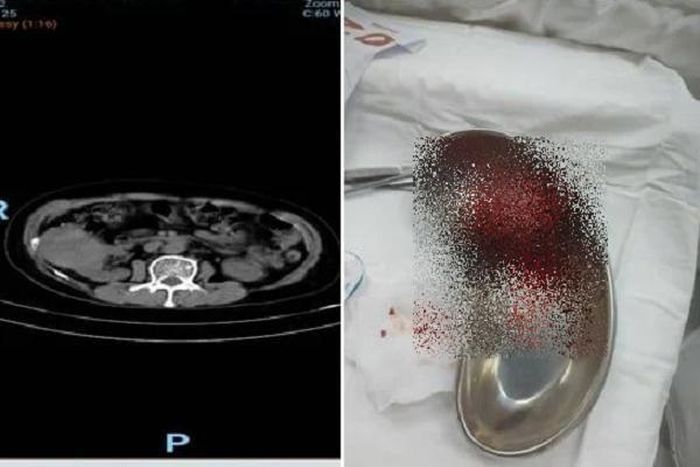

Kết quả chụp CT trước phẫu thuật (hình bên trái) và khối u thận sau khi lấy ra khỏi cơ thể bệnh nhân - Ảnh: BVCC

Các bác sĩ Bệnh viện Nhân dân 115 thực hiện siêu âm bụng thì phát hiện một khối u kích thước 75 x 60mm ở cực trên thận phải nữ bệnh nhân. Sau khi chụp CT có tiêm cản quang, khối u được chẩn đoán nghi ngờ là ung thư biểu mô tế bào thận (RCC) chưa có dấu hiệu xâm lấn ra ngoài thận trên hình ảnh học.